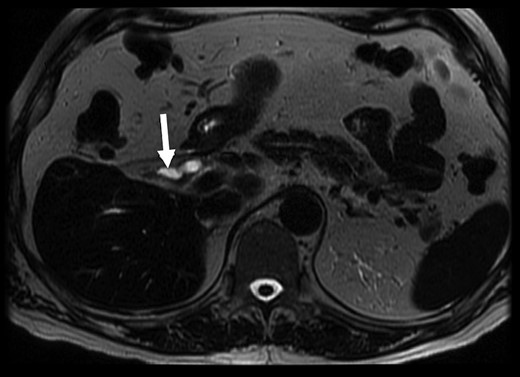

The patient then proceeded to have a magnetic resonance cholangiopancreatography (MRCP) scan for further assessment of the biliary tree. This demonstrated choledocholithiasis within the distal CBD measuring 5.9 mm. The gallbladder was reported as only seen on axial T2 weighted images (Fig. 1). The impression was the patient may have chronic cholecystitis with a shrunken gallbladder. Given the experience of the hepatobiliary surgeon involved in the case, a decision was made to proceed to laparoscopic cholecystectomy.

MRCP with suggestion of gallbladder adjacent to CBD (arrow). T2 weighted axial MRCP image, 3.0 T GE MRI.